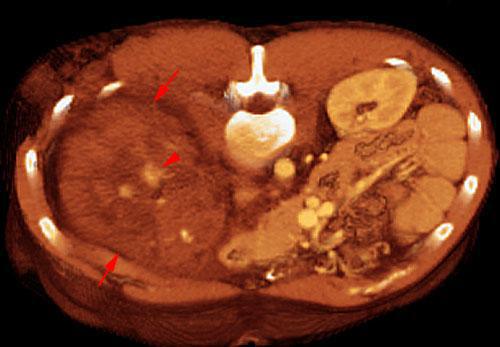

Hematoma subcapsular